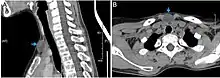

CT scan, showing a homogenous hypodense volume (unspecific cyst-like)